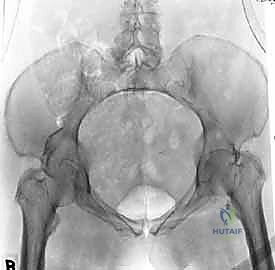

يتم تقييم المريض بشكل شامل (أشعة سينية، أشعة مقطعية ثلاثية الأبعاد) لتحديد حجم الإصابة بدقة. تُجرى العملية تحت التخدير العام لضمان استرخاء العضلات بالكامل وعدم شعور المريض بأي ألم. يتم وضع المريض على ظهره على طاولة العمليات، وتُعقم منطقة البطن والحوض بالكامل.